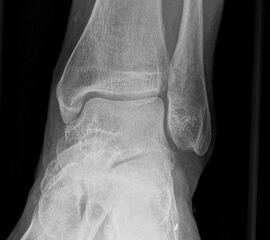

Sprunggelenk lateral mit Belastung

Positionierung:

• Der Patient steht, beide Beine sind geleichmäßig belastet.

• Der Zentralstrahl wird ist in Höhe des Gelenkspalts des OSG auf die dorsale Kante der Fibula zentriert.

• Die Kassette liegt medial dem Fuß an und ist parallel zur Fußachse ausgerichtet.

Kennzeichen des Röntgenbildes:

• Tibiagelenkfläche und Talusrolle werden exakt seitlich dargestellt, es kommt zu keinen Doppelkonturen.

• Die Fibula projiziert sich ins mittlere bis hintere Drittel der Tibiagelenkfläche.

• Die vordere und hintere Tibiakante, das Chopart-Gelenk und das Subtalargelenk kommen zur Darstellung. Das proximale Ende des Os metatarsale V ist mit abgebildet. Der Weichteilmantel (Achillessehne) ist erkennbar.

• In der belasteten Situation kommen insbesondere Verschiebungen von Talus gegenüber der Tibia zur Darstellung sowie eine Verschmälerung des Gelenkspalts.

Besondere Bemerkungen zum Beispielbild:

• Zustand nach Fremdkörperverletzung (2. Ebene zur Mortise-Aufnahme unter Belastung).

• Die röntgendichte Struktur (Metall) befindet sich plantar im Bereich des Kalkaneus.